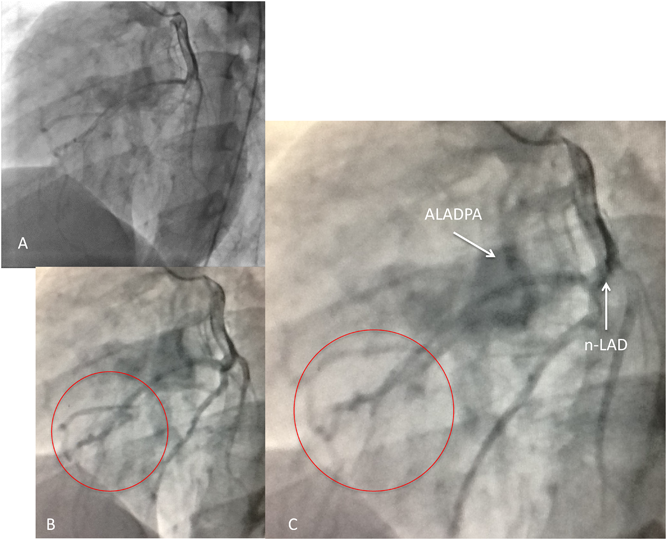

A Case of Anomalous Left Anterior Descending Coronary Artery from the Pulmonary Artery Combined with Anomalous Right Coronary Artery from the Left Coronary Sinus